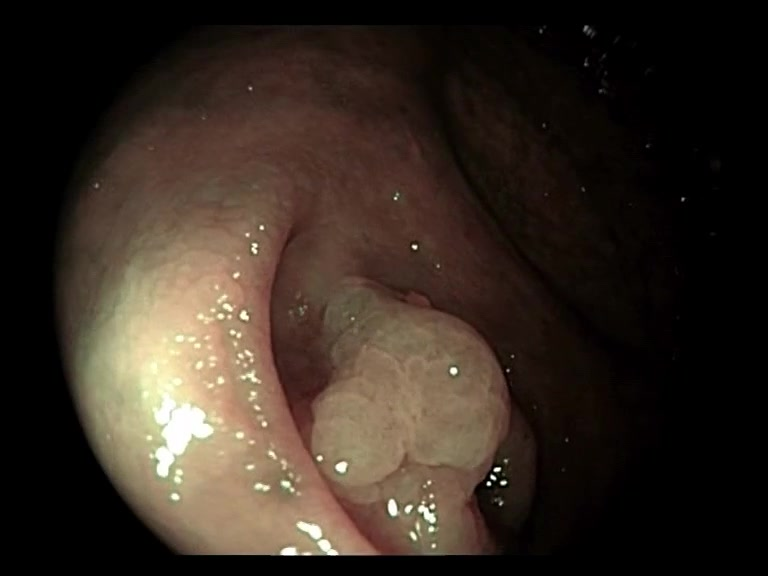

| Lesion | White Light Frame | NBI Frame | White Light Video | NBI Video | Camera Calibration |

| hyperplasic_01 |  |

|

WL.mp4 | NBI.mp4 | cam.xml |